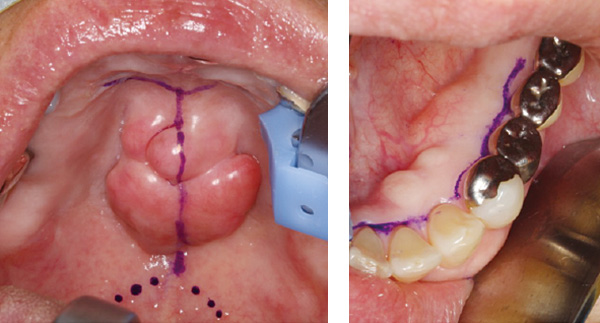

歯肉や口腔粘膜のキズが発症の原因となることもあります。キズの原因は合わない義歯、歯の詰め物・被せ物の鋭縁であることが多く、口腔内の乾燥によりキズのつくリスクが高まります。また、口蓋隆起や下顎隆起といわれる骨が突出した隆起(写真最下段)も硬い食物などでキズがつきやすい状態です。不具合のある義歯や詰め物・被せ物の調整や作り直してもらうことが必要です。口腔粘膜の乾燥については水分摂取・うがいや保湿剤を適用してください。骨隆起についてはリスクを評価し、除去(形成術)の必要性を検討してください。